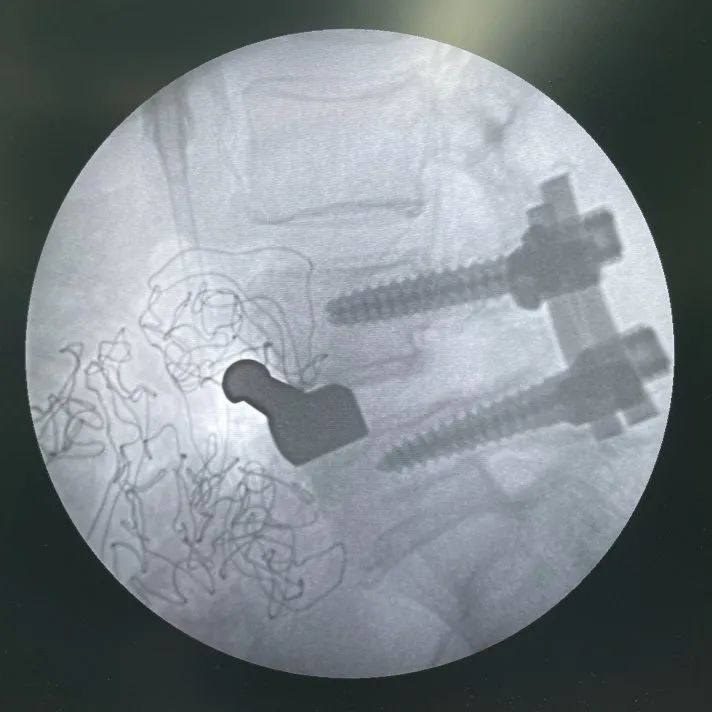

術中影像

- 取出前次不(bu)融合(he)的cage,并處理椎間隙

- L4/L5依次試用試模,確認(ren)Uni-L自穩定型腰椎融合器選用大小

- L4/L5植入Uni-L自穩定型腰椎(zhui)融合器(qi)

- 最終透視